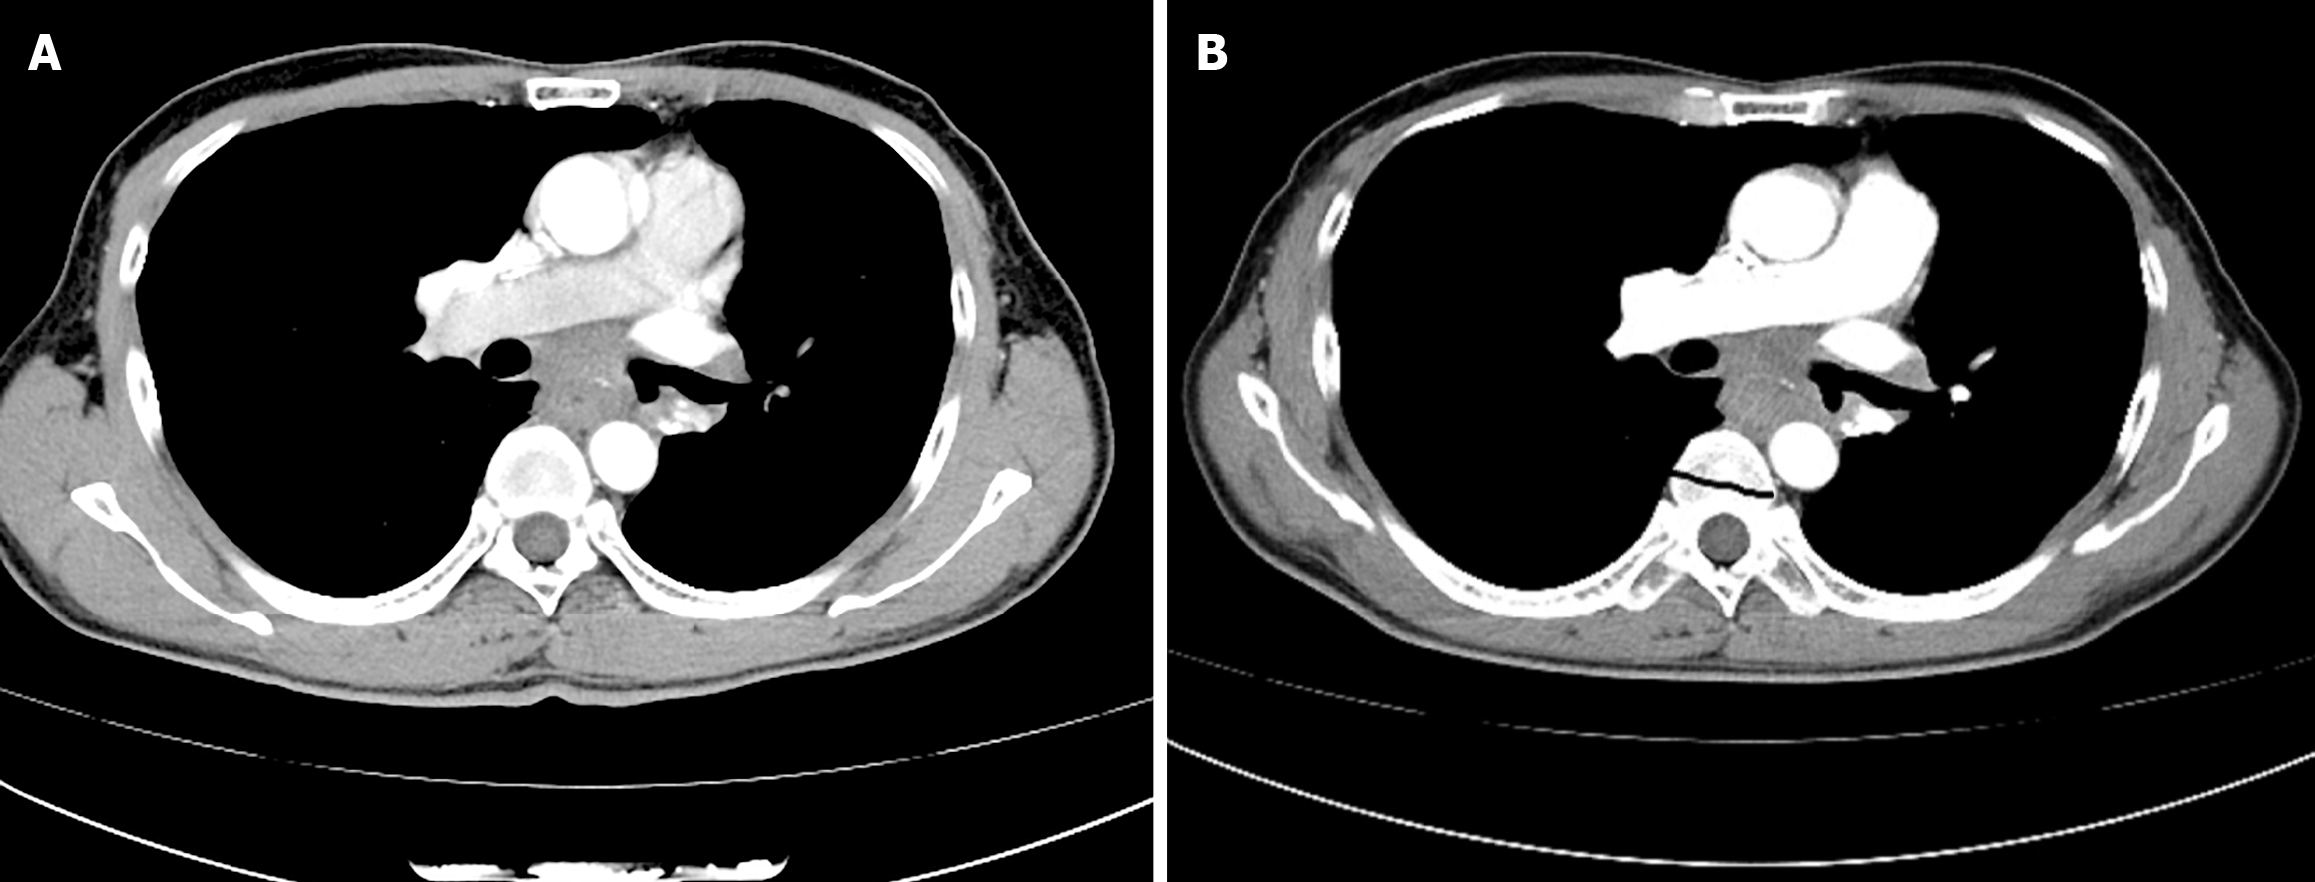

Figure 3 Chest computed tomography imaging.

A: Showing mid-esophageal wall thickening and subcarinal lymphadenopathy when the patient presented to the thoracic surgeon; B: Showing the volume of the esophageal tumor increased, causing the esophageal lumen to narrow, after two cycles of neoadjuvant immunochemotherapy.